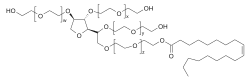

Die wesentlichen Voraussetzungen für die Hirngängigkeit der Nanopartikel ist – neben ihrer Größe – eine möglichst lange Zirkulationszeit im Blut und die passende Oberflächencharakteristik. Die Plasmahalbwertszeit wird meist durch eine PEGylierung erreicht und die Wechselwirkung am Endothel mit dem bereits beschriebenen Polysorbat.[73] Der genaue Transportmechanismus ist noch nicht endgültig geklärt. Der Polysorbat-Überzug der Partikel führt aber offensichtlich im Blutplasma zu einer Adsorption von Apolipoprotein E oder B an die Partikel. Dadurch werden die Nanopartikel als LDL-Mimetikum vom LDL-Rezeptor erkannt und in das Innere des Endothels transportiert. Danach wird der Wirkstoff entweder im Endothel freigesetzt, wodurch er per Diffusion zum Gehirn gelangen kann, oder die Partikel werden vollständig durch die abluminale Seite zum Gehirn ausgeschleust (Transzytose).[74]

Neben dem nanopartikulären Ansatz mit Polymeren sind auch nanoskalige Liposomen[79][80] und Dendrimere als potenzielle Wirkstofftransporter in der präklinischen Erprobung.[81] Besondere Beachtung findet dabei auch die im Rahmen der gesamten Nanotechnologie stattfindende Diskussion über ihre Risiken.[82]